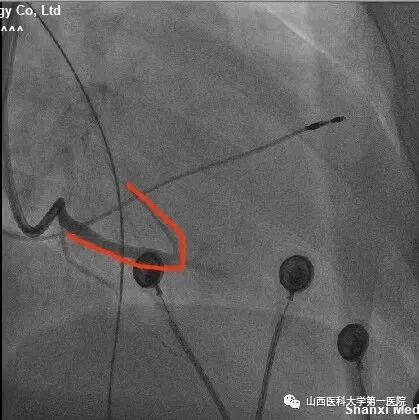

该患者为老年女性,主因反复间断胸闷10余年,加重1周入院。完善相关检查后提示:窦性心律,QRS波宽度187ms、完全左束支传导阻滞形态;心脏彩超显示:左室射血分数:25%,  左室舒末内径:72mm,符合ESC2021CRT指南I类适应证。术中,冠状窦静脉造影发现左室电极靶静脉(左室侧静脉)迂曲,双导丝导丝(Runthrough NS和Pilot50)均无法通过,采用逆向导丝技术,从后静脉逆向进入迂曲的静脉分支及侧支,成功进入左室侧静脉。

该患者冠状窦静脉侧支迂曲严重,前向无法进入左室侧静脉;同时,后静脉逆进入左室侧静脉的分支也非常迂曲,并且多处位置有膈神经刺激,左室电极多次调整,进入不同分支,并调整深度,最终寻找到起搏阈值好且无膈神经刺激位点。赵志强主任医师团队创造性的把冠脉PCI技术应用到手术中,并克服诸多困难,成功完成CRTD植入,期待患者后期心衰症状改善。